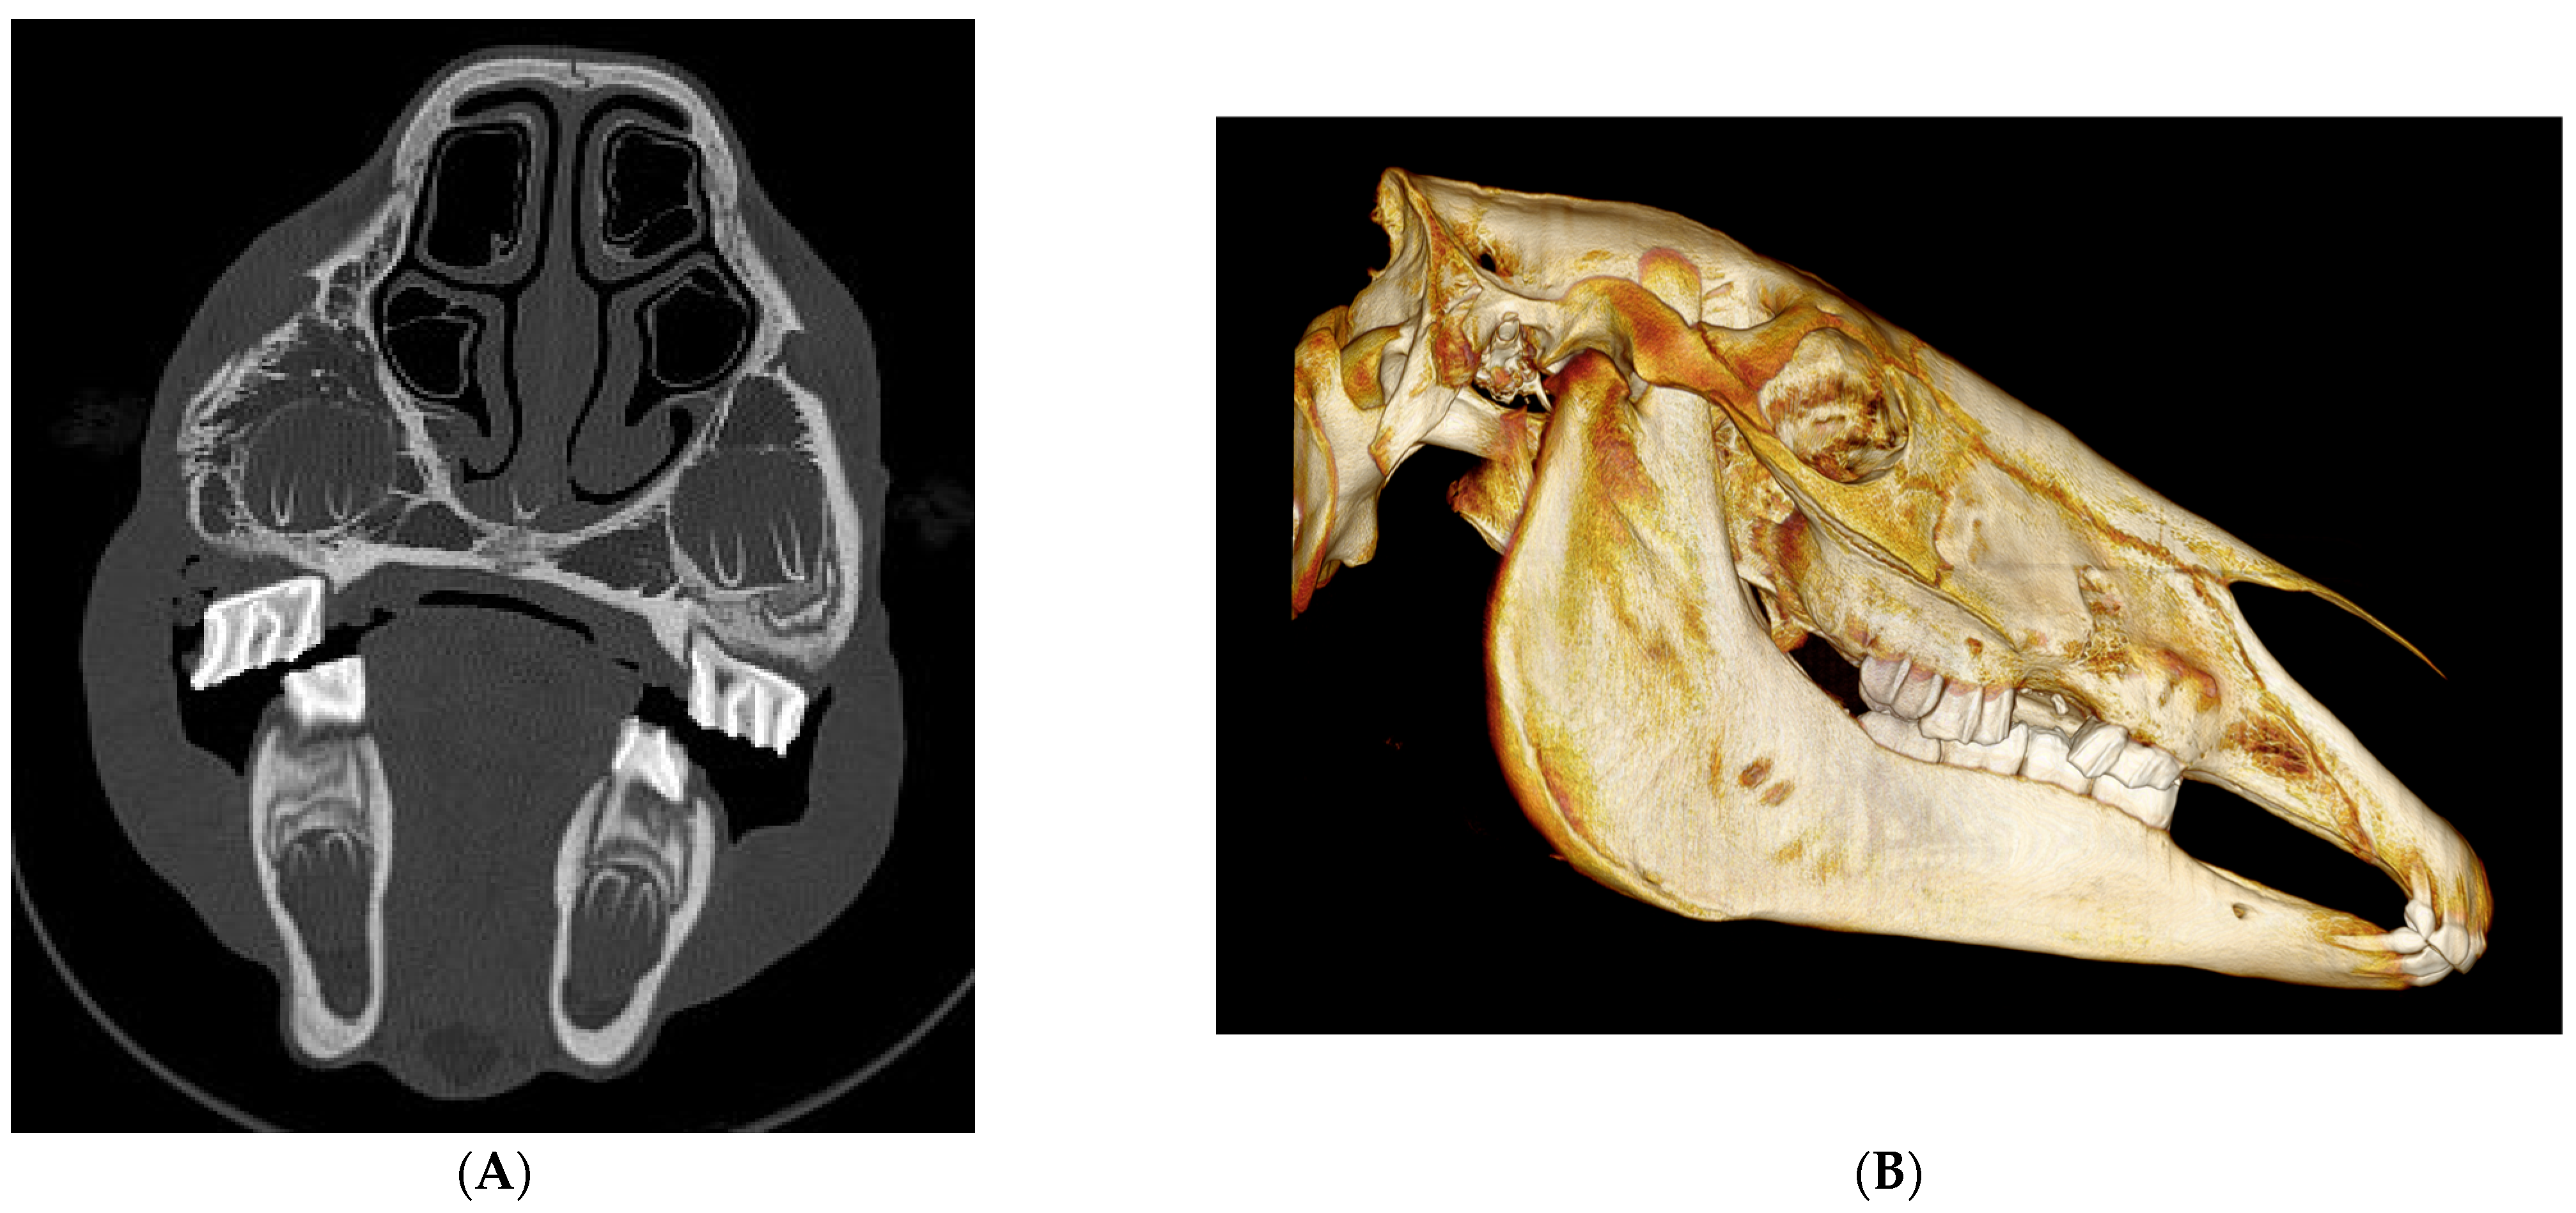

Figure 3. (A) Transverse images of head CT of 2 months old filly on presentation identifying a comminuted, open, displaced and indented complete fracture of the right maxillary bone also involving a dental structure (507); (B) 3D reconstruction of the above CT.